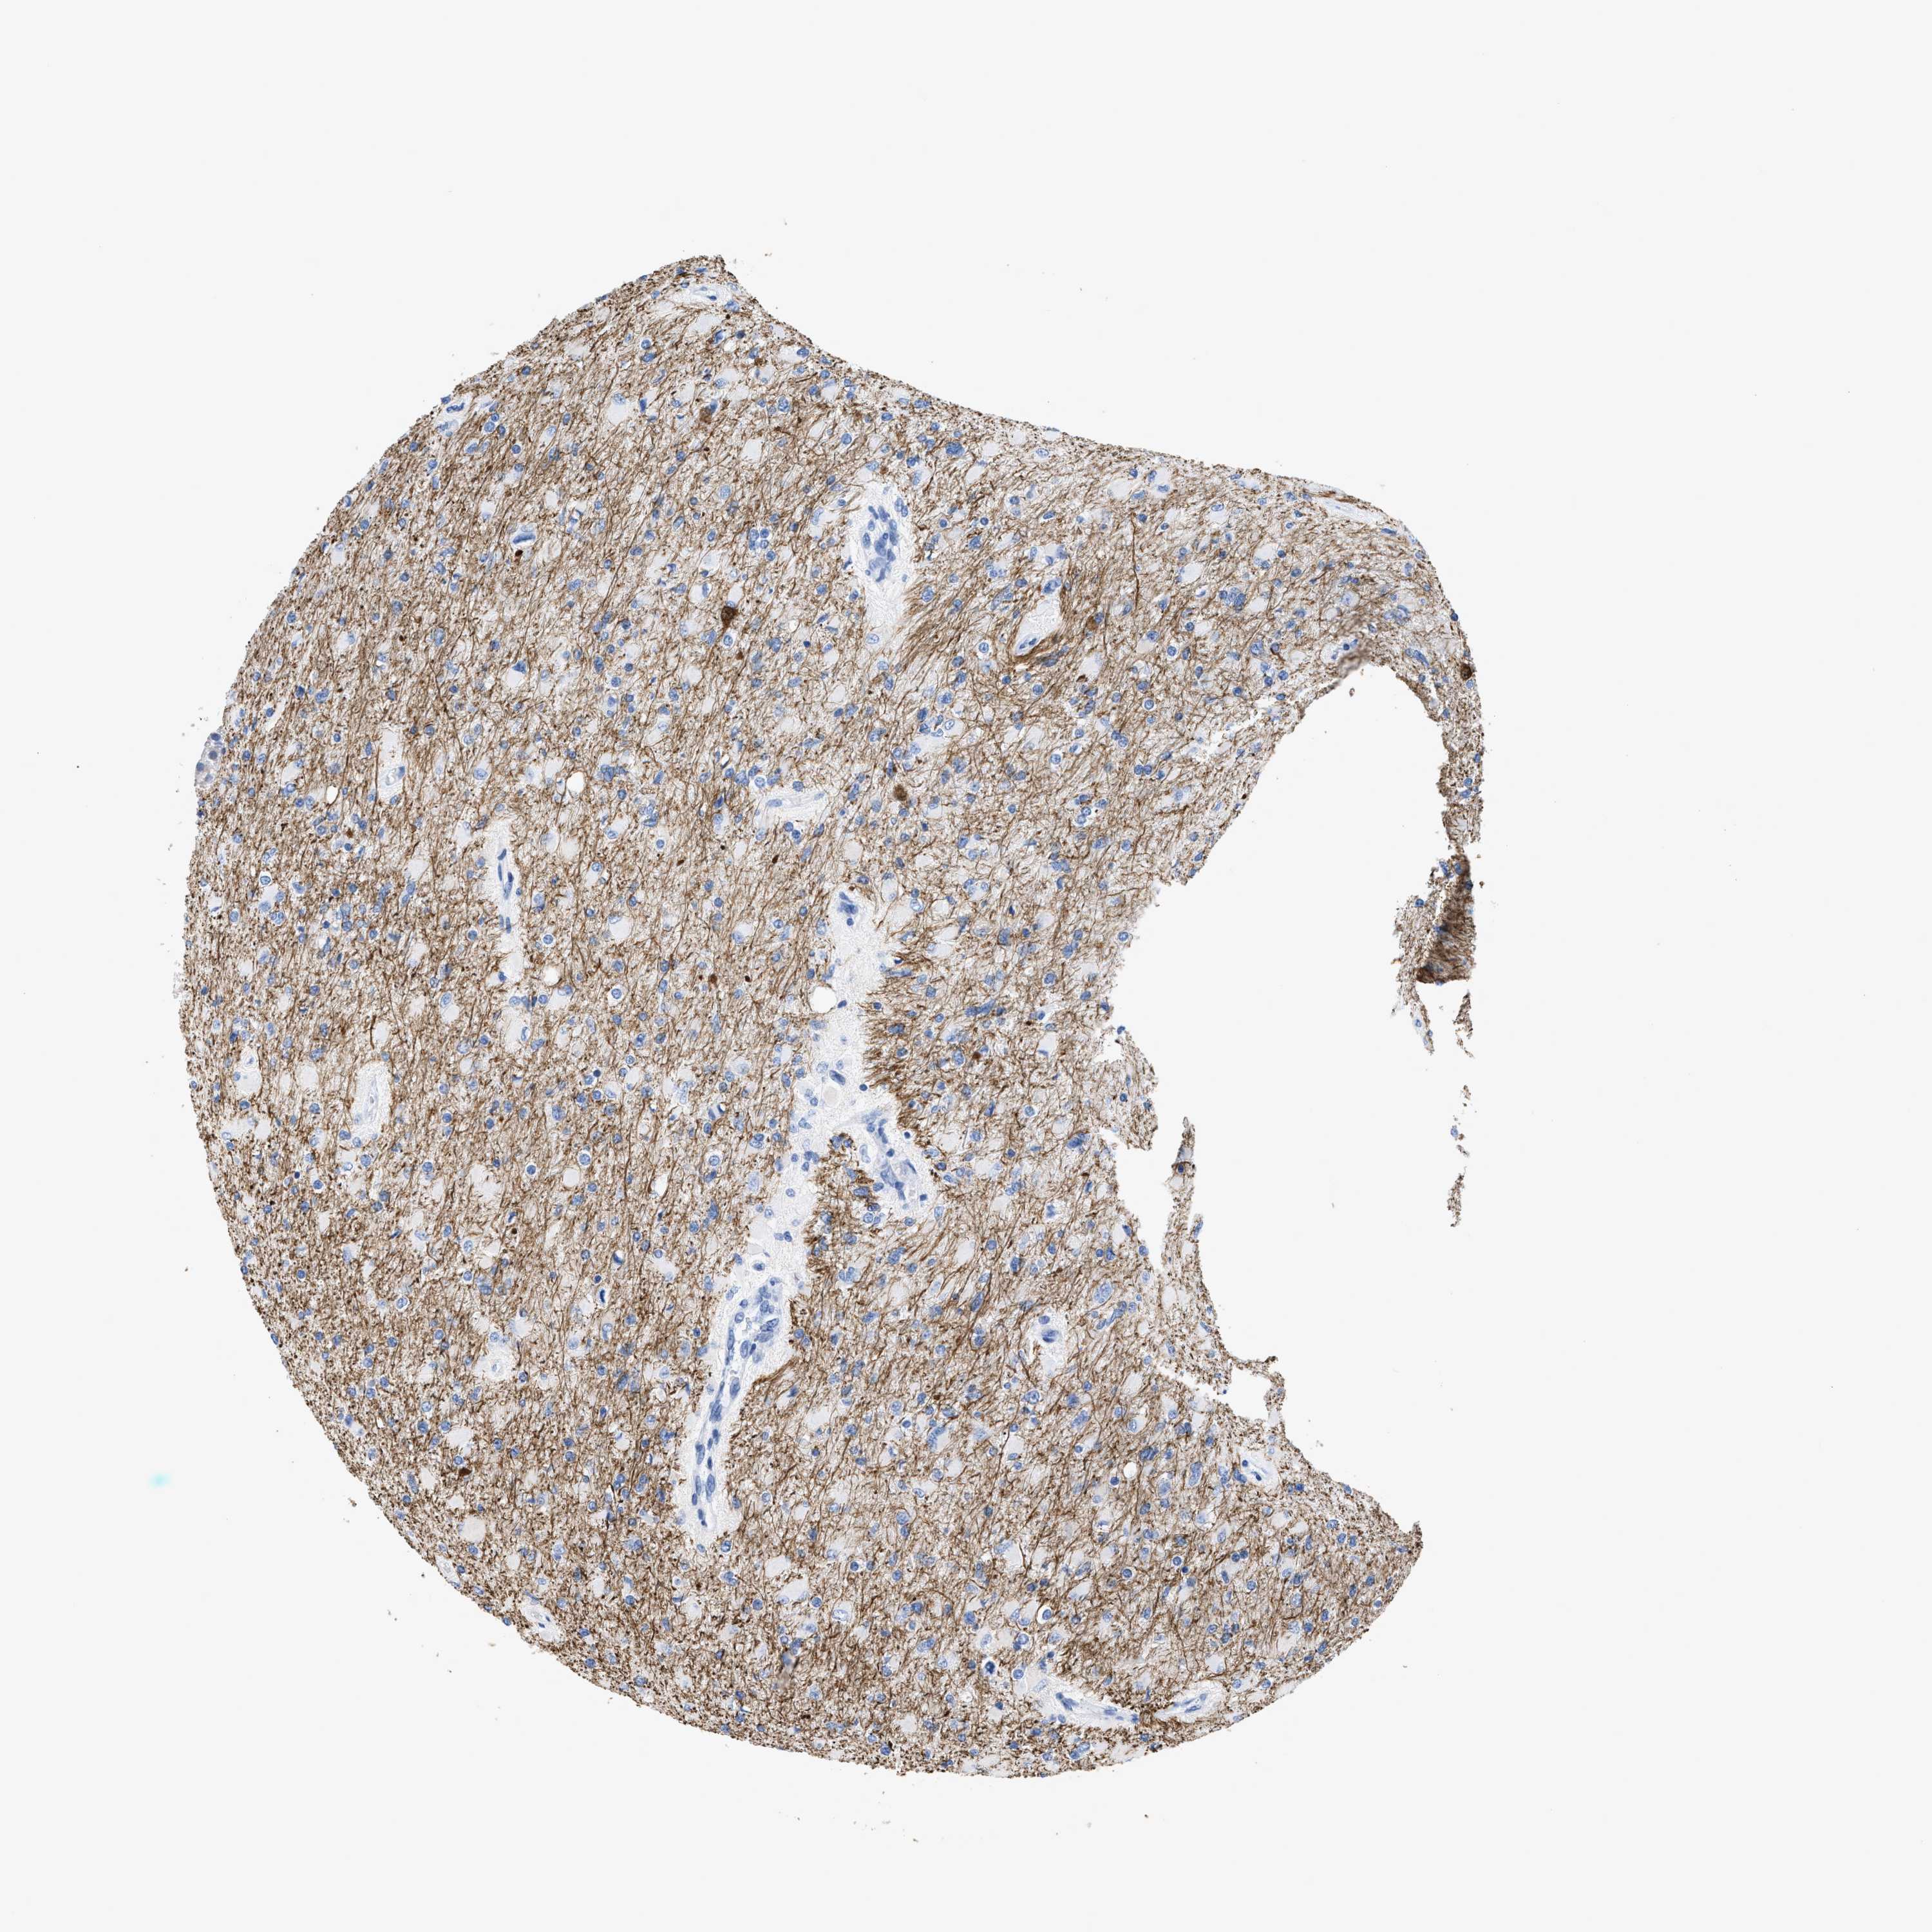

GLIOMA - Protein expressioni

A mouse-over function shows sample information and annotation data. Click on an image to view it in a full screen mode. Samples can be filtered based on level of antibody staining by selecting one or several of the following categories: high, medium, low and not detected. The assay and annotation is described here.

Note that samples used for immunohistochemistry by the Human Protein Atlas do not correspond to samples in the TCGA dataset.

Antibody stainingi

Antibody staining in the annotated cell types in the current human tissue is reported as not detected, low, medium, or high, based on conventional immunohistochemistry profiling in selected tissues. This score is based on the combination of the staining intensity and fraction of stained cells.

Each image is clickable and will lead to virtual microscopy that enables deeper exploration of all samples and also displays staining intensity scores, fraction scores and subcellular localization as well as patient and tissue information for each sample.

Antibody HPA019086

Antibody HPA030619

Staining

High

Medium

Low

Not detected

Intensity

Strong

Moderate

Weak

Negative

Quantity

>75%

75%-25%

<25%

None

Location

Nuclear

Cytoplasmic/membranous

Cytoplasmic/membranous,nuclear

Glioma, malignant, High grade

Glioma, malignant, Low grade